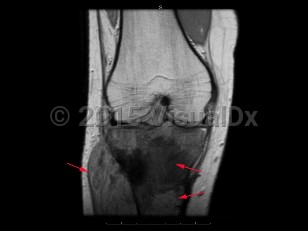

Osteosarcoma in Adult

The most common malignant tumor of bone. It arises from osteoblastic cells. Patients typically present with bone pain or a mass. The long bones are most commonly affected, and the tumor frequently metastasizes to other locations, especially the lung. Osteosarcoma is most common in males under 30 years of age. It can also occur secondary to medical conditions such as Paget disease and prior radiotherapy. Osteosarcoma is treated with chemotherapy and surgical excision of the primary tumor. With treatment, overall survival is approximately 60%-80%.